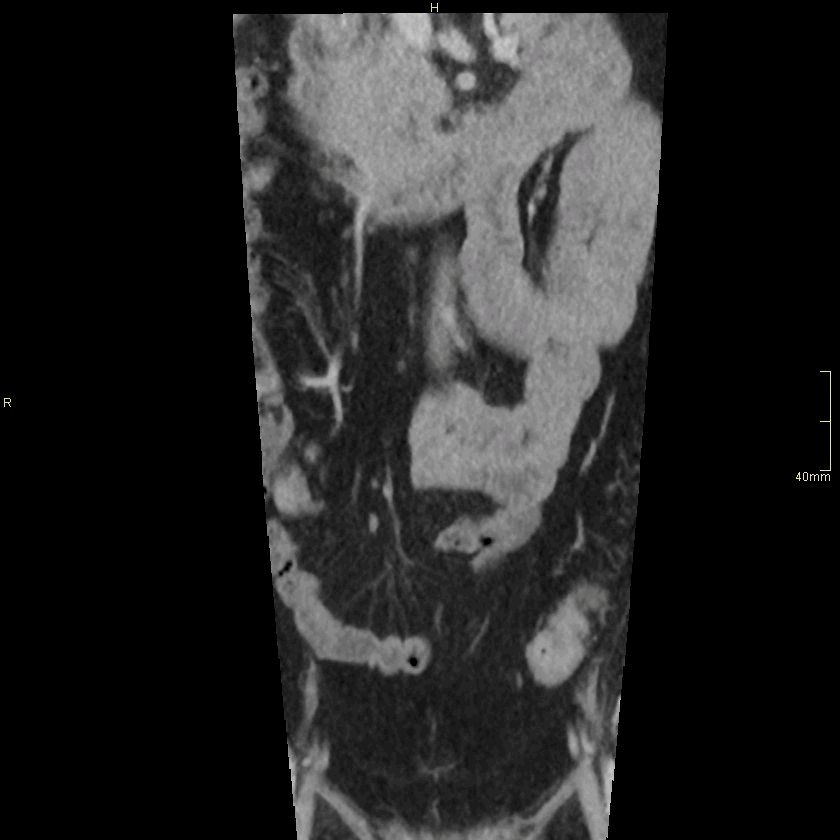

CT Lumbosacral Spine Contrast- Soft tissue window (coronal)